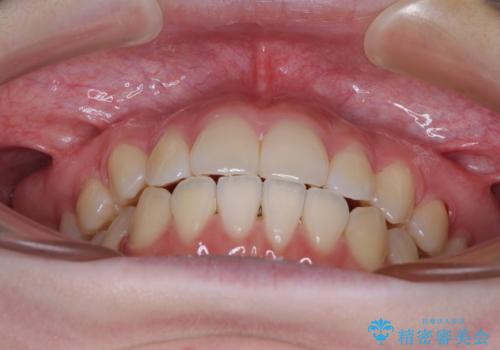

カリエール・ディスタライザーとインビザラインを用いた八重歯の改善

- 前歯の叢生と上顎左右の八重歯を気にして来院された患者様です。

奥歯の咬み合わせを見ると、左側は上顎が下顎に対して相対的に前方にあり、上下の前歯が接触していない状態でした。

咬み合わせを改善するためには、左側上顎臼歯を後方に移動させた咬み合わせにする必要があります。

インビザライン単体で改善することも可能性もありますが、インビザライン単体で達成する可能性が低いと考えられたため、カリエール・ディスタライザーという補助装置を併用して、より確実性を上げることとしました。

奥歯の咬み合わせを改善しながら、並行してインビザラインで歯列を整えることとしました。

カリエールディスタライザーを併用したことで、左側臼歯の咬み合わせを確実に改善させることができました。